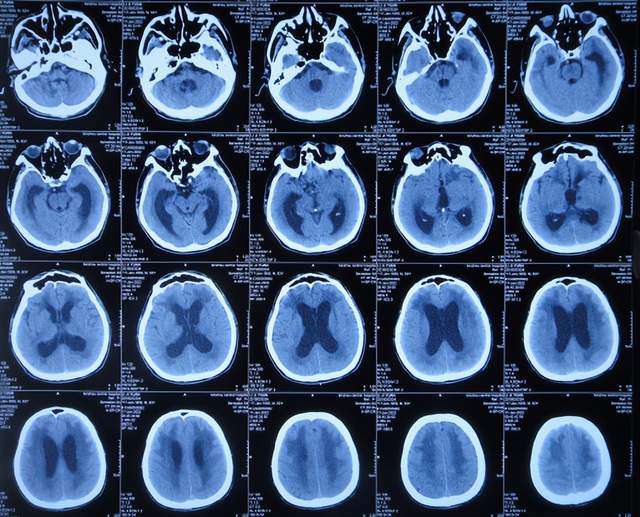

出院1个半月后,因患者病情无改善,家属想做脑室腹腔分流术,于2021年12月22日前往上级的山东省滨州市某三甲医院就诊,查头颅CT示脑积水(图-10);但腰椎穿刺检查示颅内压低;胸部CT有肺部脓肿(片子丢失),暂时给予抗感染治疗。

图-10:2021年12月22日头颅CT

给予抗感染治疗个月后即2022年1月17日,肺部脓肿明显变小(片子丢失),查头颅CT仍脑积水(图-11),未给予脑室腹腔分流术,建议暂时回家休养,但患者意识仍不好,不能走路,不能说话,体型变消瘦。

图-11:2022年1月17日头颅CT

2022年2月16日(脑出血后5个月零14天,继发脑积水4月余),为治疗脑积水,家属通过网上查询,并经确认后来到北京北亚骨科医院的李小勇脑脊液科。

入院时查头颅CT示脑积水(图-13);肺部CT示肺部感染(图-14)。

图-13:2022年2月16日头颅CT

入院次日,给予脑室外引流术,查头颅CT示脑室外引流术后状态(图-15)。

图-15:2022年2月17日头颅CT